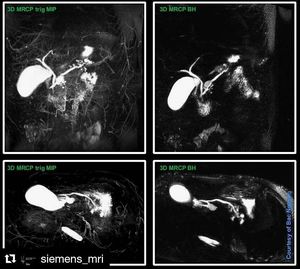

3D MRCP breath hold

Highly optimized 3D MRCP sequence within a single breath hold. Great for difficult cases where respiratory triggering fails.